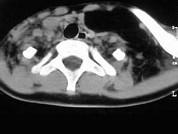

问题 女,17岁,发现左侧颈部包块半年余,PE:病灶质软,境界不清,无压痛,CT如图所示,应诊断为()

选项 A.颈部脂肪瘤 B.颈部畸胎瘤 C.颈部错构瘤 D.颈部淋巴管瘤 E.颈部陈旧性血肿

答案 A